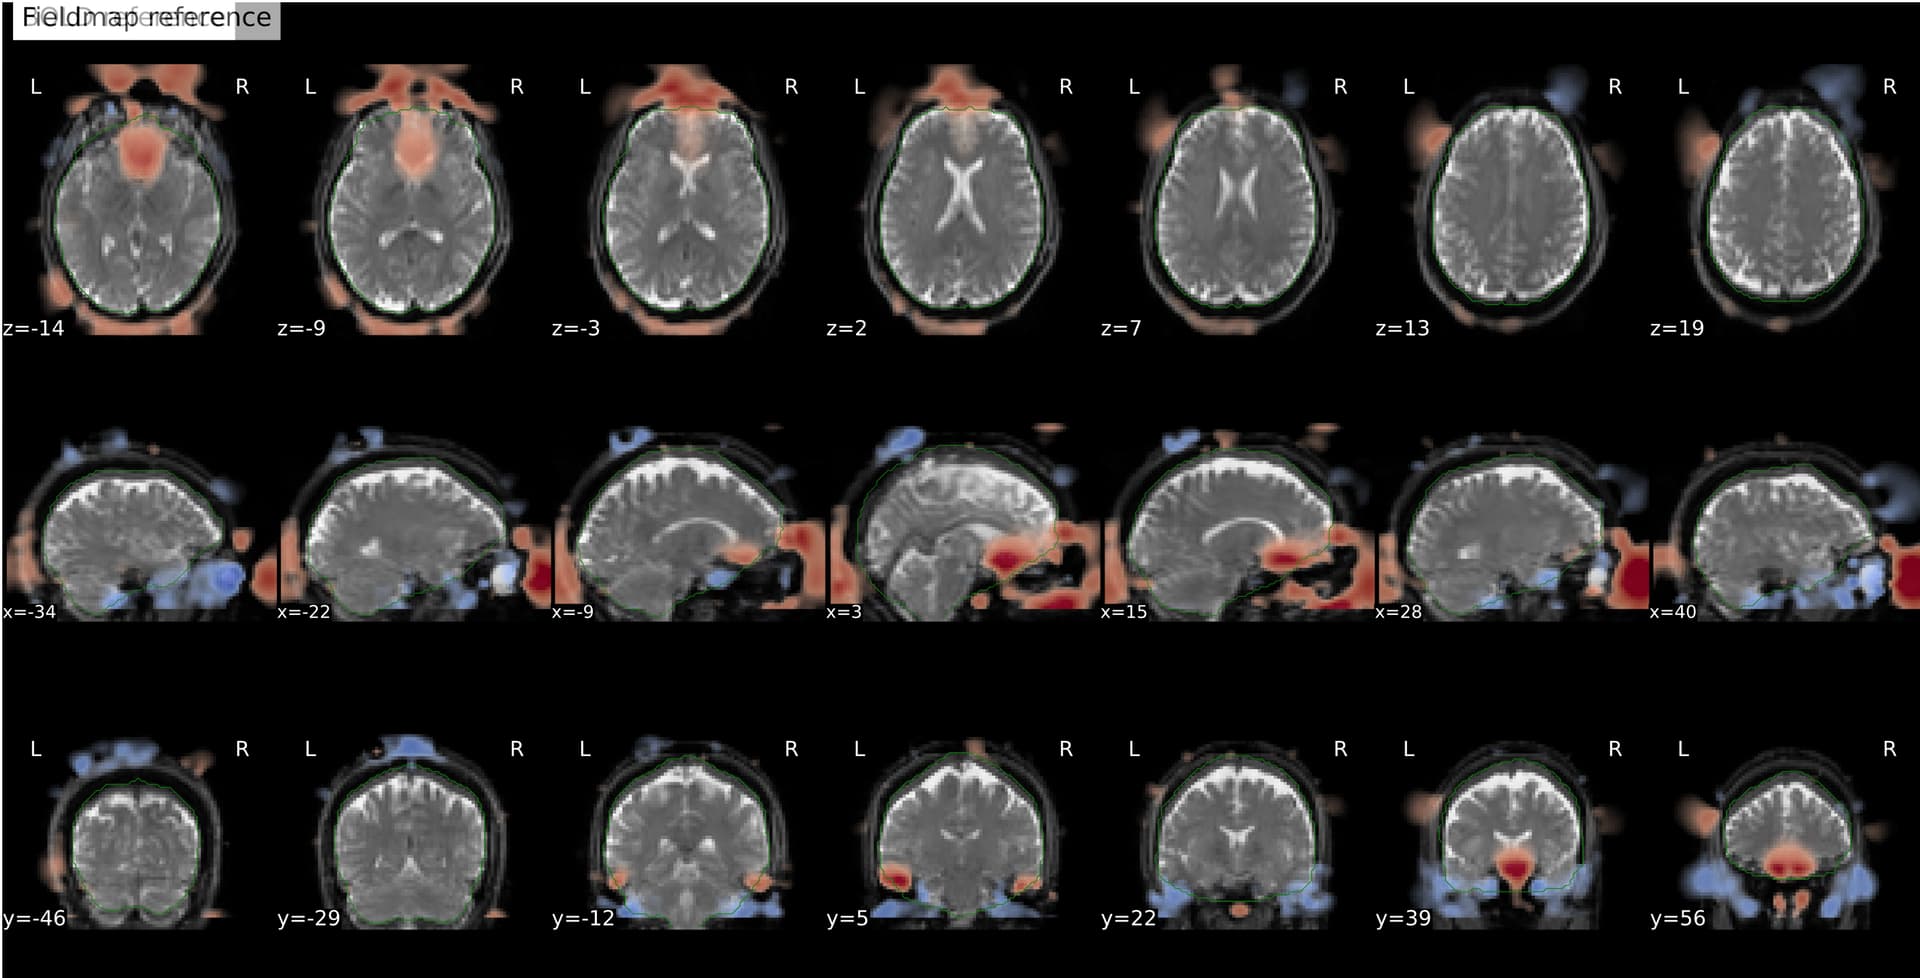

I’m seeing an apparent misalignment in the fmapCoreg reportlet for a PEPOLAR (SE-EPI AP/PA) distortion-correction workflow

- The SDC before/after panel looks okay-ish, suggesting distortion correction itself is likely working somehow, but poor than for subjects where fmap-bold coreg works as expected.